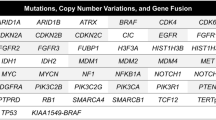

To investigate the mutational landscape of G34-DHGs, we performed WES on five fresh samples and matched peripheral blood leucocytes from our cohort. The average depths of targeted exome regions in tumors and matched blood samples were 400× and 100× , respectively. More than 98.69% of the targeted regions were covered sufficiently for confident variant calling (≥ 10× depth). We included three G34-DHG cases from the CGGA and seven G34-DHG cases from the HERBY trial (study BO25041; clinicaltrials.gov NCT01390948). The total somatic mutations of the 15 G34-DHG samples are listed in Fig. 2.

Mutation spectrum of diffuse hemispheric glioma H3 G34-mutant tumors. A The total somatic mutations of 15 diffuse hemispheric glioma H3 G34-mutant specimens. Red represents C > T/G > A mutations, blue represents C > G/G > C mutations, green represents T > C/A > G mutations, purple represents C > A/G > T mutations, orange represents T > G/A > C mutations, and yellow represents T > A/ A > T mutations. The percentages indicate the proportion of samples with the mutations. B The pathways most commonly affected by genetic mutations in diffuse hemispheric glioma H3 G34-mutant tumors included RTK-RAS, NOTCH, WNT, Hippo, PI3K, TP53, MYC and Cell_Cycle pathways. Left: histogram shows the number of mutations in each pathway. Right: histogram represent the fraction of samples affected. C Recurrent copy number alterations. GISTIC2.0 plot of recurrent focal losses (a) and gains (b). Chromosomes are represented along the vertical axis; q values are marked along the horizontal axis. The green lines mark the cut-off for the significance threshold (q = 0.25). D Schematics showing the locations of the missense mutations and truncating mutations on the PDGFRA (left), MUC16 (middle) and MUC17 (right) genes

The mutational frequencies, mutation types and clinical features of the 15 G34-DHGs are displayed in Fig. 2A. TP53 (13/15 87.0%), PDGFRA (12/15, 80.0%) and ATRX (10/15, 67.0%) were the most three frequently mutated genes. Other frequently mutated genes including MUC17 (8/15, 53.0%), MUC16 (8/15, 53.0%), MUC5B (7/15, 47.0%), MUC3A (7/15, 47.0%), OBSCN (6/15, 40.0%), SSPO (6/15, 40.0%) and DOCK3 (6/15, 40.0%) were identified by WES.

Notably, MUC family gene mutations have not been reported in G34-DHGs. The human MUC16 gene is located on chromosome 19p13.2 and the MUC17 gene is located on chromosome 7q22.1. Out of the eight cases with MUC16 mutations, 87.5% (7/8) of the cases had missense mutations, and the remaining case had a frame_shift_ins mutation. Moreover, all eight cases with MUC17 mutations had missense mutations.

Somatic SNVs and indels

A total of 8285 exonic mutations were identified in the 15 G34-DHG patients. Of these mutations, 7187 were missense mutations, 448 were nonsense mutations, 153 were frameshift deletions, 313 were frameshift insertions, 10 were in_frame_del mutations, 1 was an in_frame_ins mutation and 173 were splice site mutations. We removed 1561 silent variants with unknown function. The predominant types of nucleotide substitutions in SNVs in G34-DHGs were C > T/G > A transitions and C > A/G > T transversions.

Oncogenic pathways analysis

We identified multiple pathways of somatic mutated genes in G34-DHGs using the oncogenic pathways module of the R package maftools. Crucial signal transduction pathways included the RTK-RAS, NOTCH, WNT, Hippo, PI3K, TP53, MYC and Cell_Cycle pathways (Fig. 2B). Exome sequencing revealed that 14 of 15 cases had changes in the receptor tyrosine kinase RTK-RAS pathway, involving 42/84 pathway genes (including PDGFRA, MET, BRAF, ERF, FGFR1 and NF1). KEGG pathway analysis revealed that many of the mutated genes were involved in cancer signal transduction. Mutant genes may promote tumor cell proliferation and escape apoptosis through cascade reaction.

Copy number alterations (CNAs)

We conducted somatic CNA analyses in the five SYSUCC cases and seven HEBRY cases. The results identified recurrent gains in chromosomes 3p26.33 (11/12), 4p12 (11/12), 9q21.13 (7/12) and 9q34.11 (4/12). Recurrent losses were identified in chromosomal regions 4p35.1 (10/12), 10q25.1 (10/12), 19p13.43 (9/12), 18q23 (8/12) and 9p21.3 (7/12). Loss of somatic CNAs on chromosome 10q25 affects the largest number of genes (1330 genes), including the MGMT locus. Gains of somatic CNAs on chromosome 3p26 affects 396 genes, including ABCC5. Studies have shown that ABCC5 is associated with chemoresistance of astrocytic tumors [6].